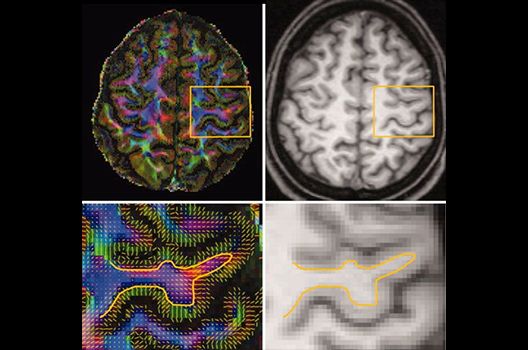

Magnetresonanztomographie

- Funktionelle Bildgebung des Gehirns (fMRT)

- MR-Diffusionstensorbildgebung (Faserbahndarstellung/fiber tracking)

Die Schwerpunkte in der MR-Forschung liegen in der multiparametrischen und funktionellen Bildgebung bei onkologischen und anderen, neuroradiologischen Fragestellungen und umfassen die Anwendung modernster MR-Verfahren sowie die Untersuchung an Hochfeld-Geräten.

Die Magnetresonanztomographie (MRT) ist ein Verfahren, bei dem durch magnetische Kräfte Bilder des Körperinneren angefertigt werden. In der Neuroradiologie können manchmal kleinste Veränderungen schwere Folgen haben; daher forschen wir an der Entwicklung hochauflösender MRT-Sequenzen, mit denen diese Prozesse und auch einzelne Nervenfaserbahnen sichtbar gemacht werden können. Darüber hinaus sind bei vielen Erkrankungen des Gehirns die Blutgefäße betroffen. Daher arbeiten wir an der Neu- und Weiterentwicklung von MRT-Sequenzen zur Darstellung der Blutgefäße und zur Blutflussanalyse (sog. „Angio-MRT“). Einen besonderen Forschungsschwerpunkt unserer Klinik stellen die MR-Protonenspektroskopie und die funktionelle MRT dar, mit denen die Analyse einzelner chemischer Substanzen im Hirngewebe oder die Darstellung ausgewählter Hirnfunktionen möglich ist.